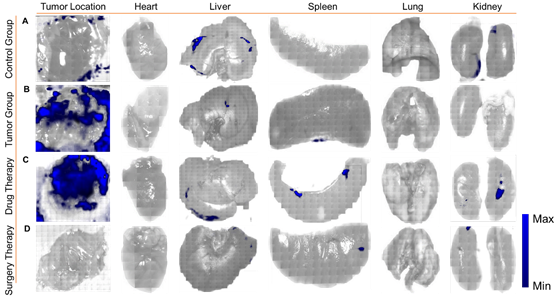

图5. 基于SERS成像的肿瘤治疗前后评估。肿瘤(健康小鼠的皮肤组织)的所有SERS成像均为活体成像,而主要器官为解剖后体外成像。(A)对照组:健康裸鼠右腋窝及器官SERS成像。(B)肿瘤组:未经任何治疗的乳腺肿瘤和器官的SERS成像。(C)药物治疗组:他莫昔芬治疗15天后乳腺肿瘤和器官的SERS成像。(D)手术治疗组:手术后乳腺肿瘤和器官的SERS成像。